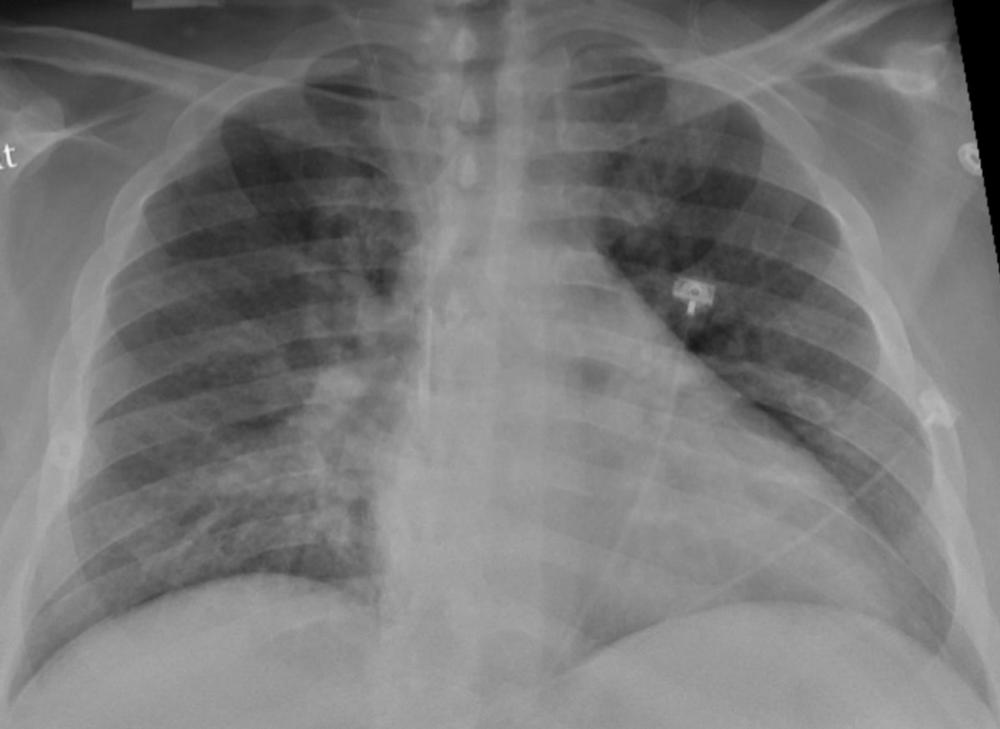

Figure 1. Chest X-ray of a SARS-CoV-2-positive patient exhibiting confusion and showing weakness on his left side shows pneumonia in the lower lungs.

High-res (TIF) version